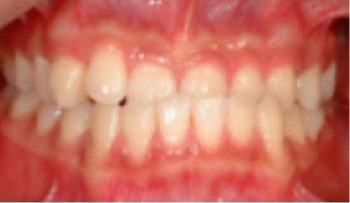

• 총생(Crowding) 치아가 삐뚤게 남.

Before

After